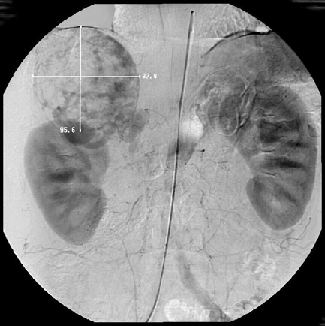

По данным различных авторов, точность ангиографической диагностики опухолей надпочечников составляет 78–95% (Kohler R. et al., 1976; Zografos G.C. et al., 1994). При правосторонней локализации опухоли, особенно больших размеров, для выявления взаимосвязи с нижней полой веной необходимо выполнение нижней каваграфии, желательно в двух проекциях (рис. 5, 6).

Рисунок 5. Нижняя каваграфия (прямая проекция) — сужение и сдавление нижней полой вены опухолью правого надпочечника

Рисунок 6. Нижняя каваграфия (боковая проекция) — оттеснение кпереди и сужение нижней полой вены опухолью правого надпочечника